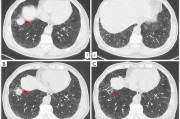

肺鳞癌化疗治疗及副作用管理详细阅读

肺鳞癌是一种恶性肿瘤,通常需要采取综合治疗方案,化疗是常用的治疗手段之一。化疗可以通过药物杀死或阻止癌细胞的增殖,帮助患者控制病情、缓解症状、提高生存率。然而,化疗也会伴随一系列副作用,如恶心、呕吐、...